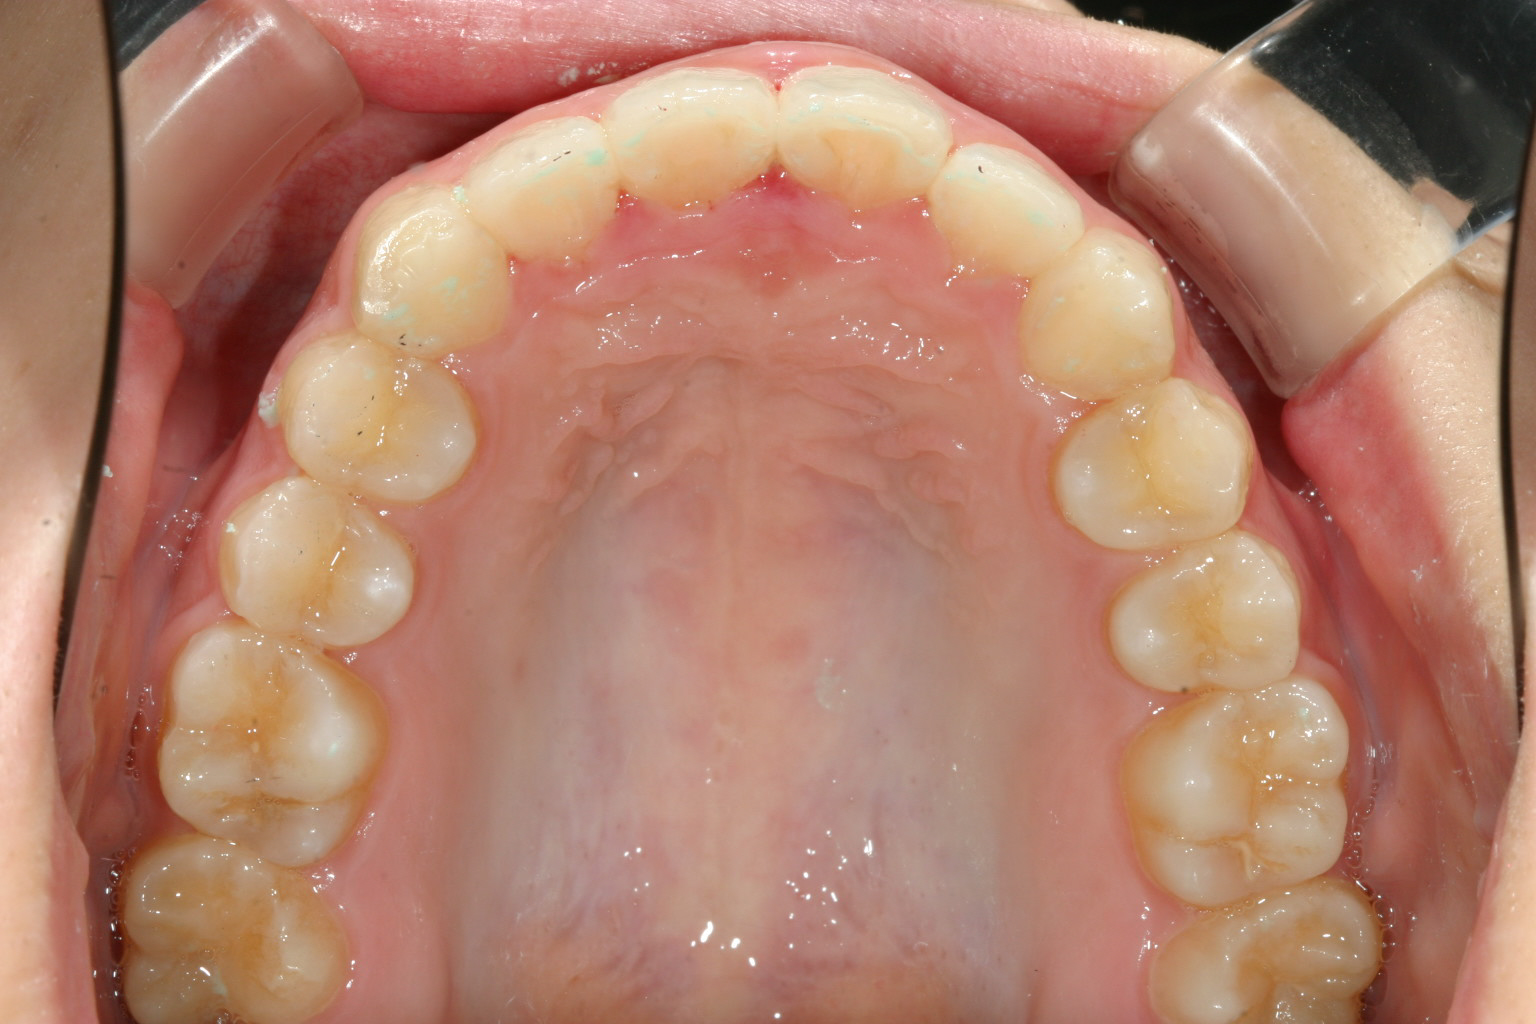

犬歯間を広げ尖ったアーチをU字に変えました。

上下の前後差が無くなりました。 綺麗なオーバージェットです。

今回のケースはアーチが尖っていた為に上下の前後差が出来、又尖った為に歯が前方に飛び出した感じ(出っ歯)になっていました。

この様なケースの場合アーチをU字に改善するのと同時にIPR(歯と歯の隙間を少し削る事)により前突感を改善致しました。